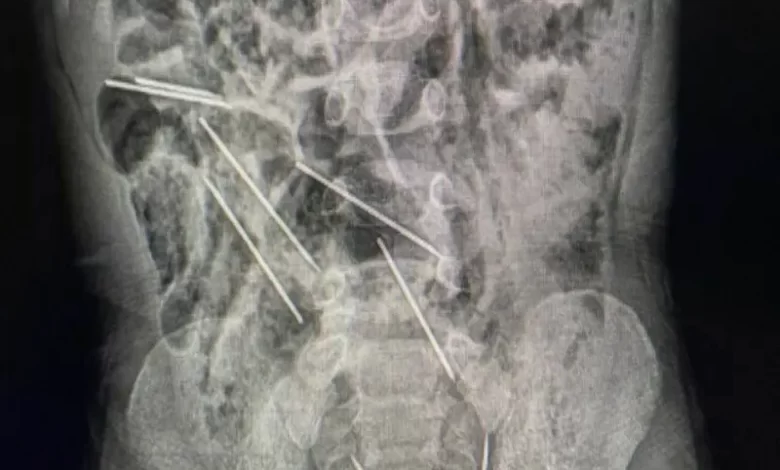

أنقذ أطباء في شمال شرقي بيرو حياة طفل، عمره عامان، بعد أن ابتلع 8 إبر حقن وهو يلعب.

وقال الطبيب إفراين سالاسار: “عندما كنا في غرفة العمليات وفتحنا بطنه وجدنا تلك القطع المعدنية، وأدركنا أنها كانت في الحقيقة إبراً”.

وذكرت وسائل إعلام محلية أن الإبر كانت من تلك التي تستخدم لتطعيم حيوانات بمزرعة تعمل فيها والدة الطفل.